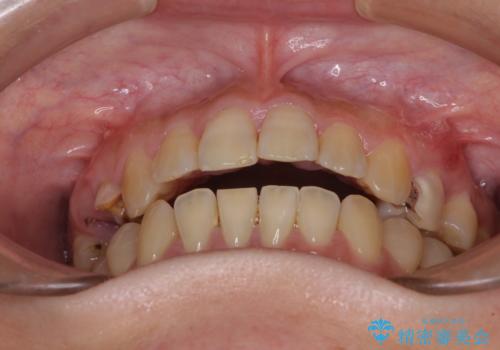

- 奥歯に問題が多くて困っているとのことで来院された患者様です。

開咬により奥歯のみが接触している状態で、前歯部にほとんど接触のない状態で、奥歯に非常に負担のかかる咬み合わせでした。

また、欠損や根管治療の必要な歯など、むし歯による問題も多く散見されました。

まずはむし歯の治療を行い、その後ワイヤー矯正にて咬み合わせを改善し、途中インプラント埋入を行い、矯正治療後に補綴治療を行うこととしました。